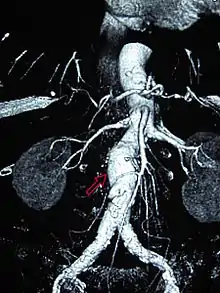

Einstein's aneurysm repair

In December 1948, Nissen admitted Albert Einstein to Jewish Hospital for removal of intestinal cysts. However, the scientist was also suffering from an abdominal aortic aneurysm (AAA).[6] An aneurysm is a dilatation that occurs in a blood vessel. In the portion of the aorta that runs through the abdomen, aneurysms are typically asymptomatic until rupture is imminent.[7] AAA rupture can cause immediate death from exsanguination.[8] Definitive surgical treatment for AAA had not been devised in the 1940s. Beginning in 1943, reinforcement with cellophane had been used to induce fibrosis in the vessel, decreasing the risk of rupture. Nissen wrapped the aneurysm with cellophane and Einstein recovered from the surgery.[6]

Upon his hospital discharge, Einstein was surrounded by photographers and he was photographed with his tongue sticking out at them. He sent an autographed newspaper clipping of the photo to Nissen with the inscription "To Nissen my tummy / The world my tongue."[9] Einstein lived for several years after Nissen wrapped his AAA in cellophane.[6] Einstein died in a Princeton, New Jersey hospital in 1955. Initial news reports listed gallbladder inflammation as the cause of death.[10] However, his medical team had suspected gallbladder irritation resulting from a leaking AAA.[11] An autopsy conducted by pathologist Thomas Harvey showed that he died of a leaking AAA.[12]